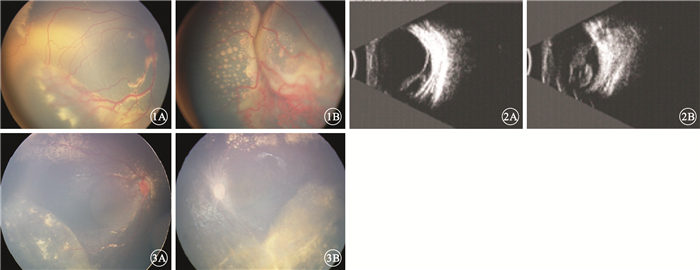

患兒男,1歲。因家長發現患兒視力差不能追物20余天于2013年10月30日來我院眼科就診。患兒發育正常,否認早產及吸氧史、家族相關遺傳病史。全身檢查未見異常。眼科檢查:視力不配合。右眼眼壓17 mmHg(1 mmHg=0.133 kPa),左眼眼壓12 mmHg。雙眼白瞳癥,其余眼前節檢查未見異常。雙眼玻璃體輕度混濁;視網膜可見異常血管增生,顳下方視網膜血管紆曲,末梢血管呈囊樣擴張;視網膜下大量黃白色滲出,視網膜內大量膽固醇結晶。右眼顳側、下方視網膜呈灰白色隆起;左眼視網膜呈灰白色隆起(圖 1)。B型超聲檢查,右眼下方、顳側視網膜脫離,其下可見少量回聲光點;左眼玻璃體腔光帶與視盤相連,視網膜全脫離(圖 2);雙眼未見明確占位病變。外院CT檢查,左眼球較右眼球略大,形態欠規整,右眼球形態尚可。雙眼眼球內可見形態不規則的軟組織密度影,未見明顯鈣化灶;晶狀體形態密度、視神經眼外肌未見明顯異常;肌椎內外間隙未見異常密度影。臨床診斷:(1)雙眼Coats病(右眼3A期,左眼3B期);(2)雙眼滲出性視網膜脫離。明確診斷并完善相關檢查,因患兒眼底視網膜脫離較高,無法激光光凝,征得患兒家屬同意并簽署知情同意書,2013年11月25日給予雙眼玻璃體腔分別注射抗血管內皮生長因子(VEGF)藥物雷珠單抗0.3 mg。此后分別間隔半個月進行3次重復注射治療;2015年1月28日因左眼恢復不理想,給予冷凍、經鞏膜外脈絡膜上腔放液聯合玻璃體腔注射雷珠單抗0.3 mg;3月17日再次雙眼玻璃體腔注射雷珠單抗0.3 mg。5月6日復查,雙眼視網膜灰白色隆起消失;視網膜異常增生的血管明顯消退,仍可見少量黃白色滲出及膽固醇結晶;左眼視盤顏色較淡,其周圍視網膜血管較細(圖 3)。B型超聲檢查,雙眼玻璃體混濁,未見視網膜脫離。治療及隨訪過程中未見與藥物和治療方式相關的眼部和全身并發癥。

雙眼治療前彩色眼底病像。1A.右眼;1B.左眼。視網膜可見異常血管增生,顳下方視網膜血管紆曲,末梢血管呈囊樣擴張;視網膜下可見大量黃白色滲出,視網膜內大量膽固醇結晶??圖 2雙眼治療前B型超聲像。2A.右眼,下方、顳側視網膜脫離,其下可見少量回聲光點;2B.左眼,玻璃體腔內楓葉樣光帶與視盤相連,視網膜全脫離??圖 3雙眼治療后彩色眼底像。3A.右眼;3B.左眼。雙眼視網膜灰白色隆起均已消失,可見少量黃白色滲出及膽固醇結晶;左眼視盤顏色較淡,其周圍視網膜血管較細

雙眼治療前彩色眼底病像。1A.右眼;1B.左眼。視網膜可見異常血管增生,顳下方視網膜血管紆曲,末梢血管呈囊樣擴張;視網膜下可見大量黃白色滲出,視網膜內大量膽固醇結晶??圖 2雙眼治療前B型超聲像。2A.右眼,下方、顳側視網膜脫離,其下可見少量回聲光點;2B.左眼,玻璃體腔內楓葉樣光帶與視盤相連,視網膜全脫離??圖 3雙眼治療后彩色眼底像。3A.右眼;3B.左眼。雙眼視網膜灰白色隆起均已消失,可見少量黃白色滲出及膽固醇結晶;左眼視盤顏色較淡,其周圍視網膜血管較細

患兒男,1歲。因家長發現患兒視力差不能追物20余天于2013年10月30日來我院眼科就診。患兒發育正常,否認早產及吸氧史、家族相關遺傳病史。全身檢查未見異常。眼科檢查:視力不配合。右眼眼壓17 mmHg(1 mmHg=0.133 kPa),左眼眼壓12 mmHg。雙眼白瞳癥,其余眼前節檢查未見異常。雙眼玻璃體輕度混濁;視網膜可見異常血管增生,顳下方視網膜血管紆曲,末梢血管呈囊樣擴張;視網膜下大量黃白色滲出,視網膜內大量膽固醇結晶。右眼顳側、下方視網膜呈灰白色隆起;左眼視網膜呈灰白色隆起(圖 1)。B型超聲檢查,右眼下方、顳側視網膜脫離,其下可見少量回聲光點;左眼玻璃體腔光帶與視盤相連,視網膜全脫離(圖 2);雙眼未見明確占位病變。外院CT檢查,左眼球較右眼球略大,形態欠規整,右眼球形態尚可。雙眼眼球內可見形態不規則的軟組織密度影,未見明顯鈣化灶;晶狀體形態密度、視神經眼外肌未見明顯異常;肌椎內外間隙未見異常密度影。臨床診斷:(1)雙眼Coats病(右眼3A期,左眼3B期);(2)雙眼滲出性視網膜脫離。明確診斷并完善相關檢查,因患兒眼底視網膜脫離較高,無法激光光凝,征得患兒家屬同意并簽署知情同意書,2013年11月25日給予雙眼玻璃體腔分別注射抗血管內皮生長因子(VEGF)藥物雷珠單抗0.3 mg。此后分別間隔半個月進行3次重復注射治療;2015年1月28日因左眼恢復不理想,給予冷凍、經鞏膜外脈絡膜上腔放液聯合玻璃體腔注射雷珠單抗0.3 mg;3月17日再次雙眼玻璃體腔注射雷珠單抗0.3 mg。5月6日復查,雙眼視網膜灰白色隆起消失;視網膜異常增生的血管明顯消退,仍可見少量黃白色滲出及膽固醇結晶;左眼視盤顏色較淡,其周圍視網膜血管較細(圖 3)。B型超聲檢查,雙眼玻璃體混濁,未見視網膜脫離。治療及隨訪過程中未見與藥物和治療方式相關的眼部和全身并發癥。

雙眼治療前彩色眼底病像。1A.右眼;1B.左眼。視網膜可見異常血管增生,顳下方視網膜血管紆曲,末梢血管呈囊樣擴張;視網膜下可見大量黃白色滲出,視網膜內大量膽固醇結晶??圖 2雙眼治療前B型超聲像。2A.右眼,下方、顳側視網膜脫離,其下可見少量回聲光點;2B.左眼,玻璃體腔內楓葉樣光帶與視盤相連,視網膜全脫離??圖 3雙眼治療后彩色眼底像。3A.右眼;3B.左眼。雙眼視網膜灰白色隆起均已消失,可見少量黃白色滲出及膽固醇結晶;左眼視盤顏色較淡,其周圍視網膜血管較細

雙眼治療前彩色眼底病像。1A.右眼;1B.左眼。視網膜可見異常血管增生,顳下方視網膜血管紆曲,末梢血管呈囊樣擴張;視網膜下可見大量黃白色滲出,視網膜內大量膽固醇結晶??圖 2雙眼治療前B型超聲像。2A.右眼,下方、顳側視網膜脫離,其下可見少量回聲光點;2B.左眼,玻璃體腔內楓葉樣光帶與視盤相連,視網膜全脫離??圖 3雙眼治療后彩色眼底像。3A.右眼;3B.左眼。雙眼視網膜灰白色隆起均已消失,可見少量黃白色滲出及膽固醇結晶;左眼視盤顏色較淡,其周圍視網膜血管較細